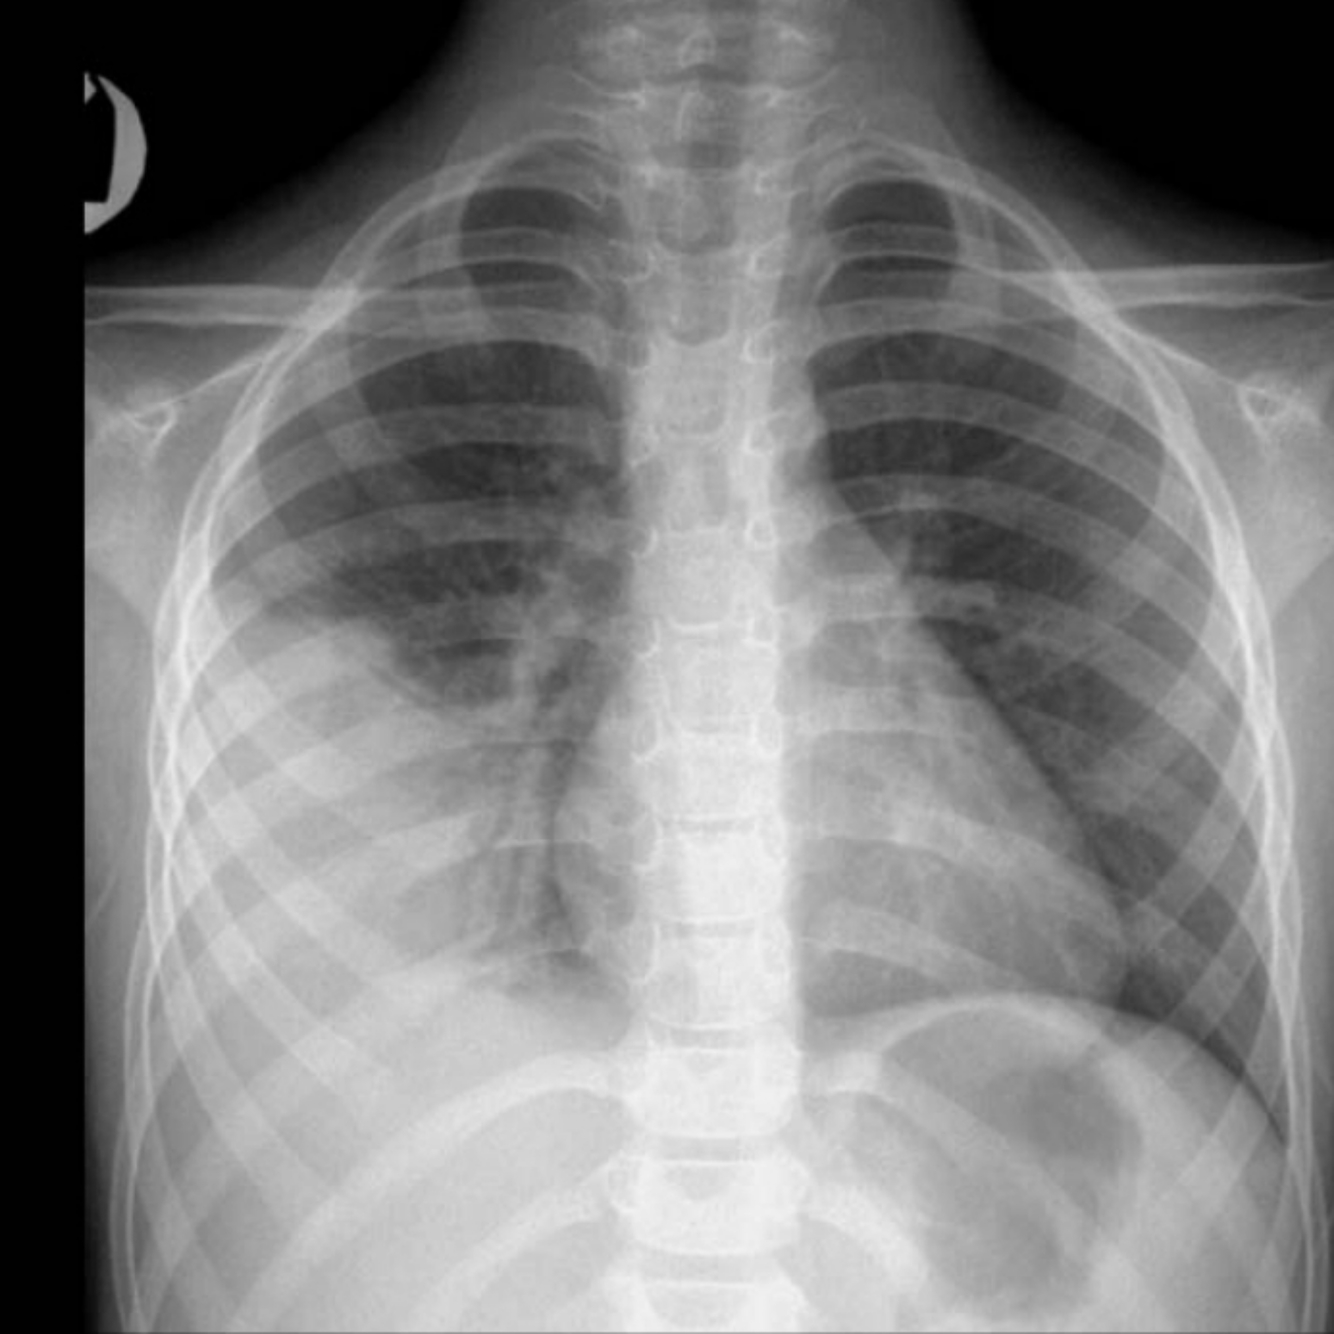

CXR: Frontal chest radiograph shows right lower lobe consolidation and the silhouette sign—the adjacent diaphragm is obscured, the right cardiac silhouette, anterior to the consolidation, is preserved.

Diagnosis: Right lower lobe pneumonia.